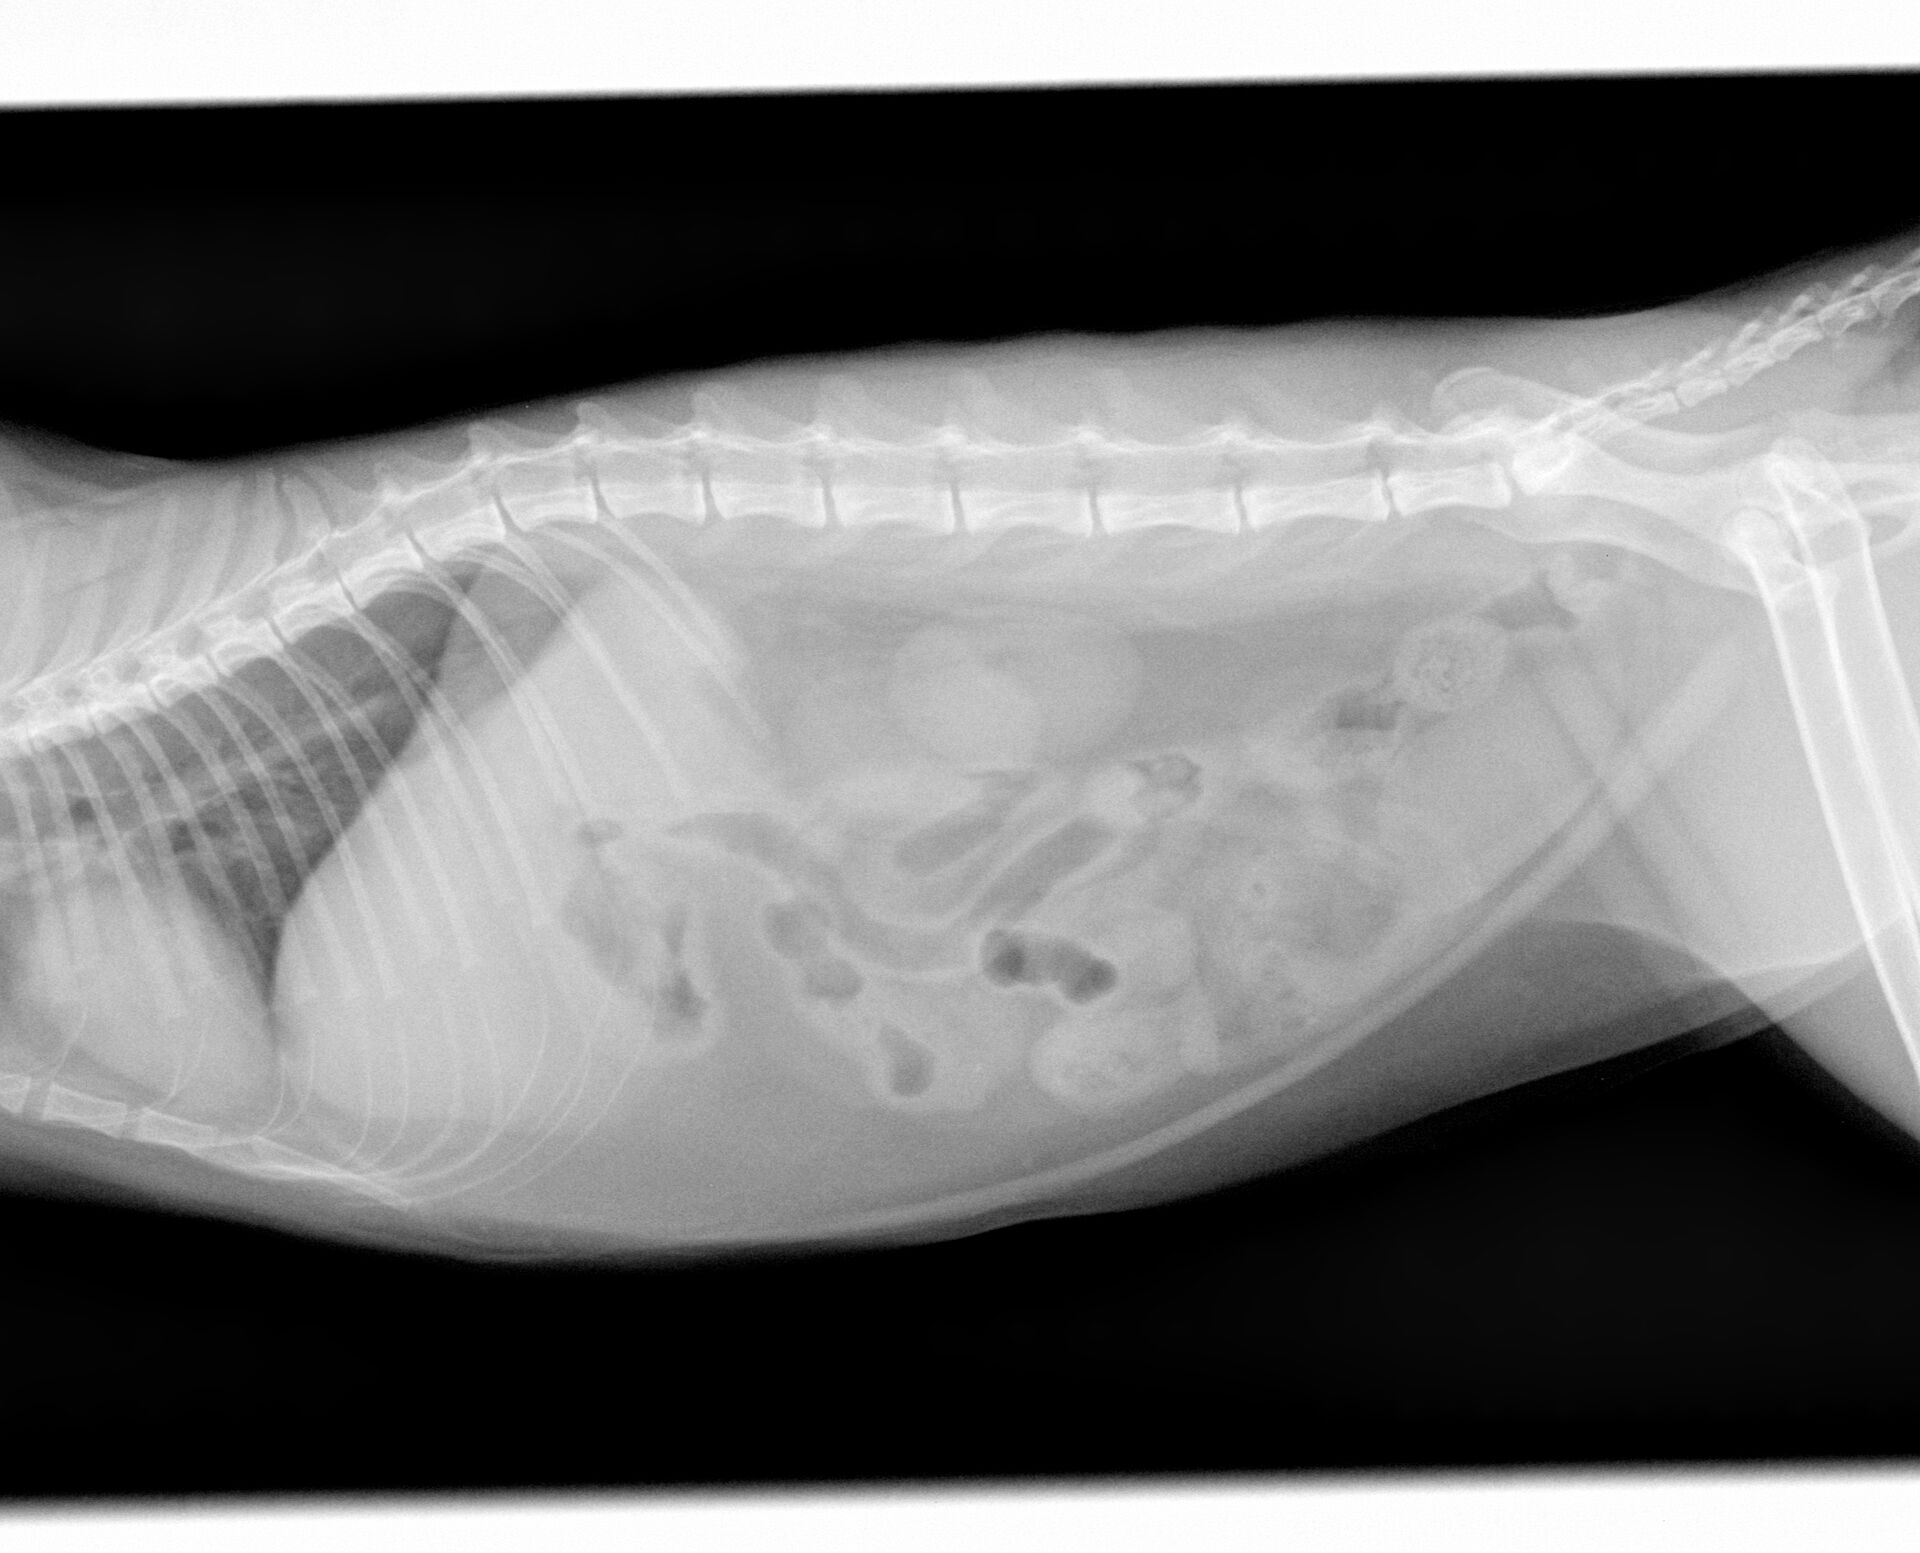

小腸を切開し右の写真の紐状のものを取り出して縫合しました。

この後、3日間入院して点滴した後、食欲が出てきて嘔吐もなかったので、退院としました。